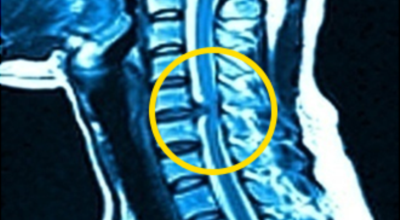

목디스크 증상이 나타날때 빨리 발견하여 비수술 치료를 받고 꾸준히 관리하는 것이 베스트이죠. 목디스크 환자 중 수술을 진행하는 환자는 2% 미만으로 현저히 적다고 해요. 수술을 진행하는 경우는 감각이 느껴지지 않는 마미증후군이나, 한쪽 다리가 눈에 띌 정도로 야윈 경우에만 진행하므로 올바른 자세 교정만으로도 충분히 호전될 수 있는 질병이죠. 목에 연관된 검사는 MRI나 CT를 이용해요. 그러나 전자의 경우 비용이 굉장히 비싸기 때문에 디스크 증세가 확실하다고 생각될 경우에만 선택적으로 하고 의무적으로 하는 건 아니니까 비용에 대해선 부담을 가지지 마시길 바래요.

목디스크 증상으로 인해 3개월 이상 약물이나 물리치료를 해도 효과가 없을 경우 수술을 고려해야 해요. 통증이 심해서 일상생활에 지장이 있거나, 신경증상이 악화되고 근력도 함께 줄어들 때와 큰 디스크가 탈출해 중추신경인 척수를 압박해 척수증이 발생하는 경우에도 수술을 고려할 수 있어요.